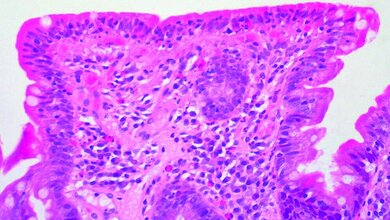

Als mögliche Auslöser der Leiden gelten FODMAPs (fermentierbare Oligo-, Di- und Monosaccharide sowie Polyole). Das sind Zucker, die aus 1–14 Zuckermolekülen bestehen und im Dünndarm nicht ausreichend abgebaut werden können. Daher gelangen sie unverdaut in den Dickdarm und können dort Probleme verursachen. Vor allem bestimmte Mehlbestandteile (Fructane) sorgen dafür, dass sich große Mengen Wasserstoff, Kohlendioxid und Methan bilden. Die Gase blähen den Darm auf und bereiten große Schmerzen.